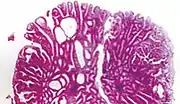

| Villous adenoma | 15%[16] to 40%[15] | Over 75% villous[14] | ![]() | |

Micrograph of a villous adenoma. These polyps are considered to have a high risk of malignant transformation. H&E stain.